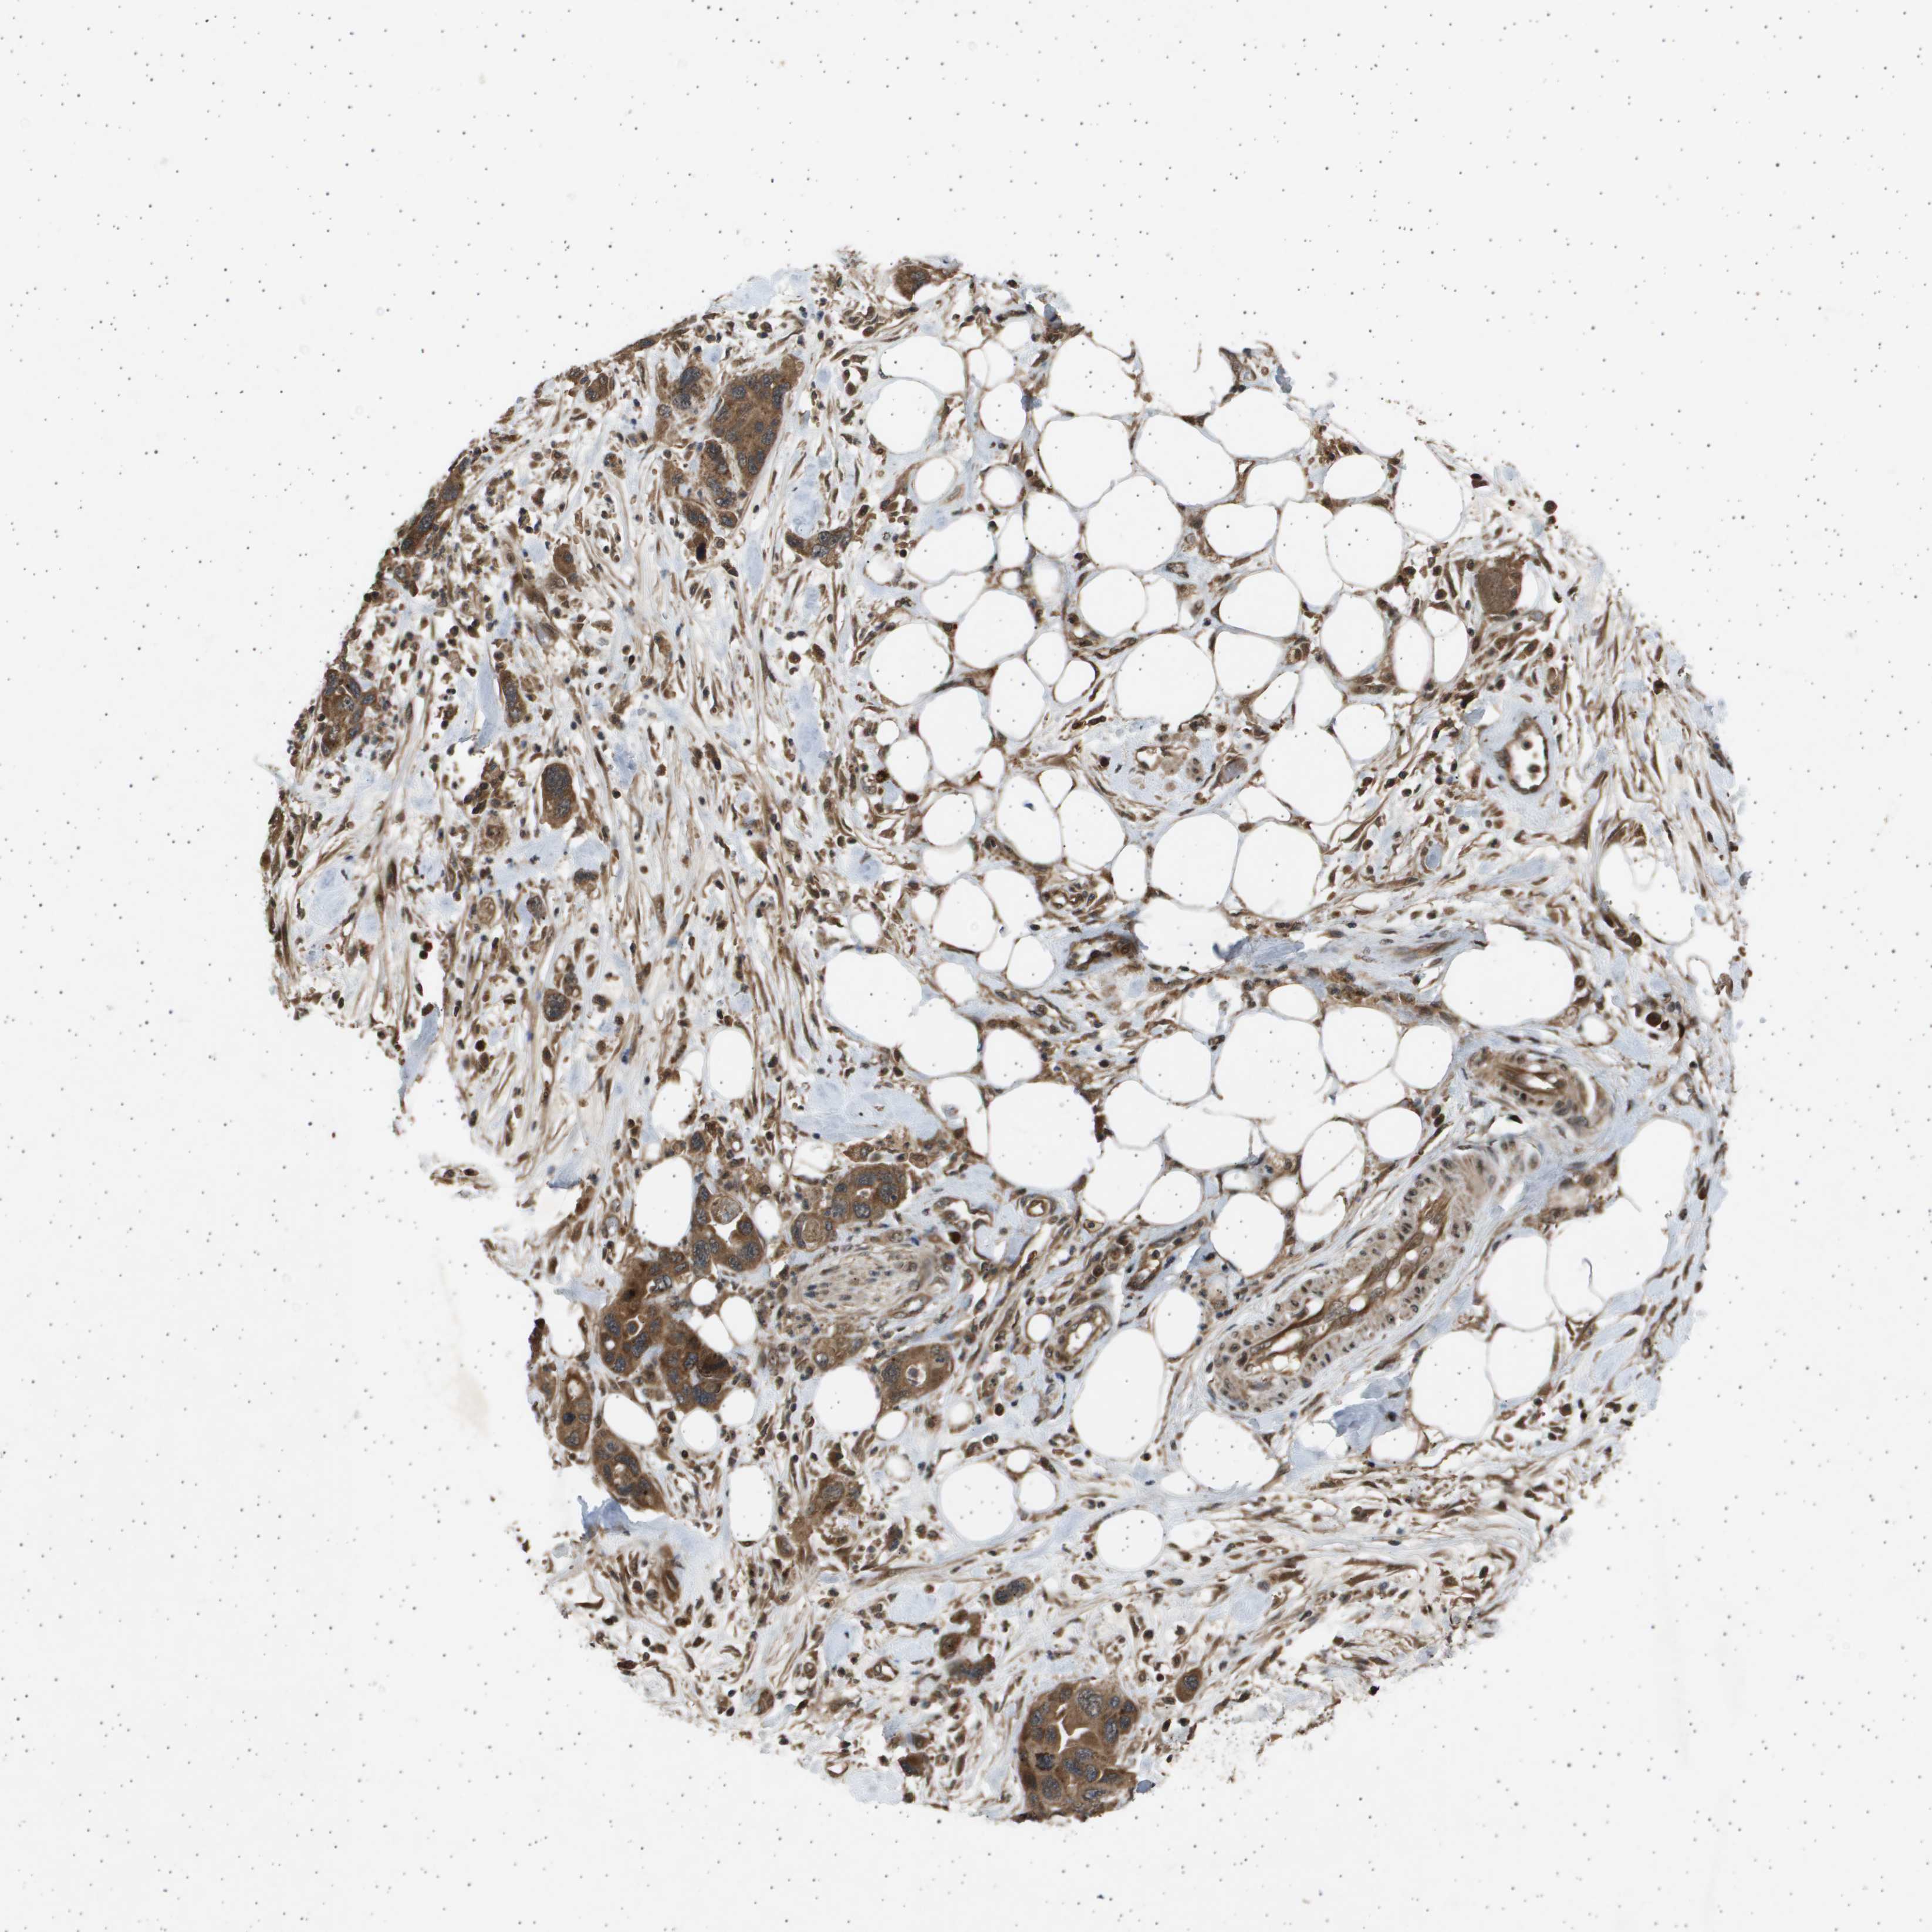

PANCREATIC CANCER - Protein expressioni

A mouse-over function shows sample information and annotation data. Click on an image to view it in a full screen mode. Samples can be filtered based on level of antibody staining by selecting one or several of the following categories: high, medium, low and not detected. The assay and annotation is described here.

Note that samples used for immunohistochemistry by the Human Protein Atlas do not correspond to samples in the TCGA dataset.

Antibody stainingi

Antibody staining in the annotated cell types in the current human tissue is reported as not detected, low, medium, or high, based on conventional immunohistochemistry profiling in selected tissues. This score is based on the combination of the staining intensity and fraction of stained cells.

Each image is clickable and will lead to virtual microscopy that enables deeper exploration of all samples and also displays staining intensity scores, fraction scores and subcellular localization as well as patient and tissue information for each sample.

Antibody HPA017869

Staining

High

Medium

Low

Not detected

Intensity

Strong

Moderate

Weak

Negative

Quantity

>75%

75%-25%

<25%

None

Location

Nuclear

Cytoplasmic/membranous

Cytoplasmic/membranous,nuclear

Adenocarcinoma, NOS